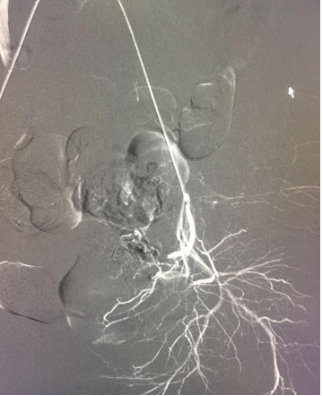

该患者孕囊位于子宫切口处肌壁内,且该处肌层菲薄,厚约3.75px(如图1,2,3)。出血风险及子宫穿孔风险极大。为了保留生育功能,确保患者生命安全,我院妇科积极发起多学科联合诊疗(MDT)会议,特邀请放射科、麻醉科、超声科等相关科室开展讨论,一致决定先由放射科行子宫动脉栓塞术并灌注甲氨蝶呤杀胚治疗(微创介入),72小时之内再行清宫术。最终,该患者在放射科顺利完成甲氨蝶呤灌注和双侧子宫动脉栓塞(如图4-5)的情况下,第二天由妇科在超声科床旁监护下成功完成清宫术(如图6),宫腔镜检查宫腔及切口处无异常。术中出血仅有5ml(出血量较常规清宫术明显减少),并于术后第三天康复出院。

图1:切口妊娠-孕囊与肌层关系

image.png

图2:切口妊娠-孕囊大小